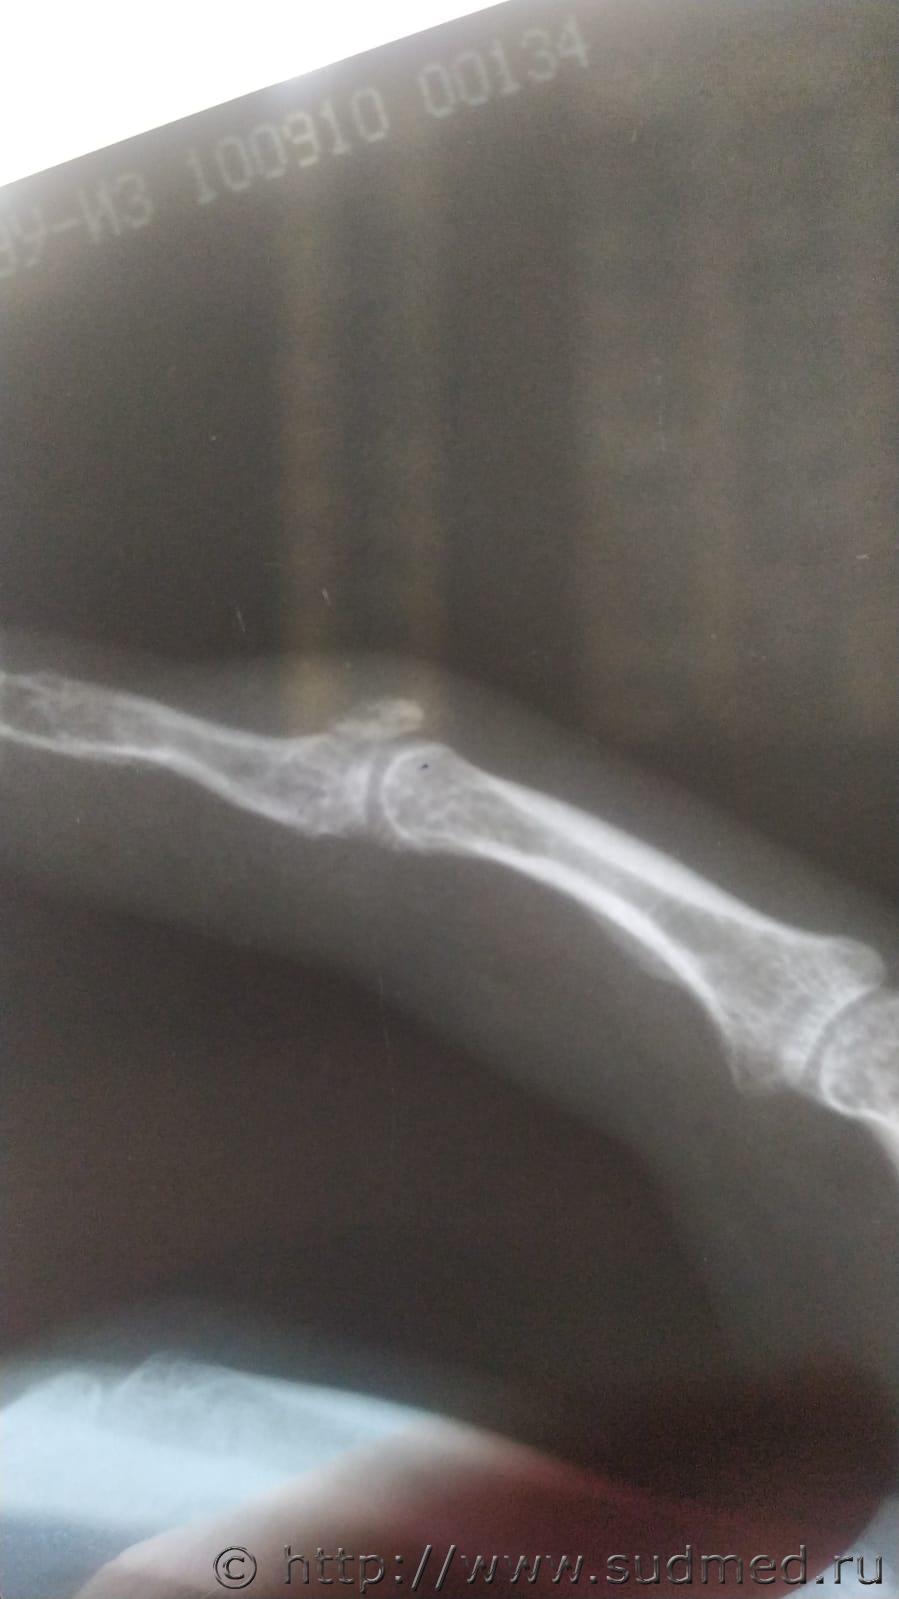

Прошу Вас, можно ли определить перелом на этих двух снимках?

На втором снимке четко виден внутрисуставной перелом проксимального эпифиза ногтевой фаланги, без смещения. Не понимаю, как такую четкую линию просветвления можно не заметить...

Полностью согласен. По первому снимку его можно подозревать - неоптимальная проекция, но деконфигурация в зоне перелома заметная (было целесообразно выполнить контрольный снимок).